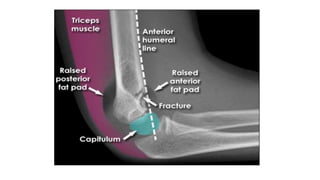

1. Fad pad sign :

 In undisplaced fracture the ‘fad pad’ or ‘sail’ sign should raise

suspicion.

 This is a triangular lucency in front of & behind the distal humerus

like the sail of a yacht, due to the fad pad being pushed by fluid such

as a hematoma.

2. Anterior humeral line:

 A line drawn along the anterior cortex of the humerus should cross

the middle of the capitellum.

 If the line is anterior to the capitellum, a type-II # is suspected.

X-ray 1. Fad padsign :  In undisplaced fracture the ‘fad pad’ or ‘sail’ sign should raise suspicion.  This is a triangular lucency in front of & behind the distal humerus like the sail of a yacht, due to the fad pad being pushed by fluid such as a hematoma. 2. Anterior humeral line:  A line drawn along the anterior cortex of the humerus should cross the middle of the capitellum.  If the line is anterior to the capitellum, a type-II # is suspected.